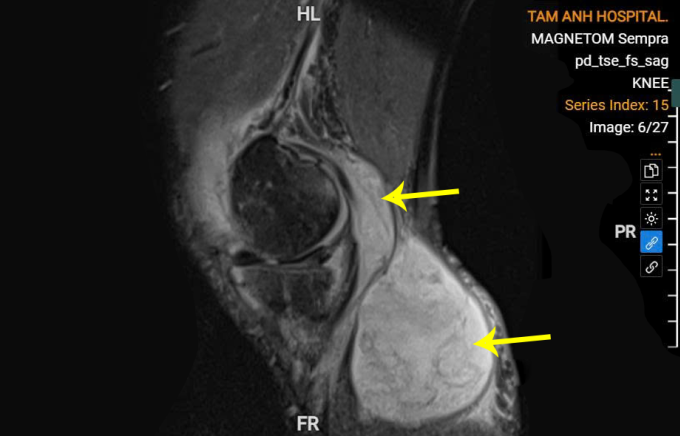

Ông Trịnh bị viêm đa khớp, đau khớp, u bao hoạt dịch khớp gối nhiều năm. Xét nghiệm máu tại Bệnh viện Đa khoa Tâm Anh Hà Nội cho thấy chỉ số bạch cầu, CRP và procalcitonin tăng cao. Siêu âm, chụp cộng hưởng từ ghi nhận dịch mủ, phía sau gối có u bao hoạt dịch lớn 5x10 cm chứa đầy dịch mủ đục.

U bao hoạt dịch chứa ổ mủ lớn sau khớp gối ông Trịnh. Ảnh: Bệnh viện Đa khoa Tâm Anh